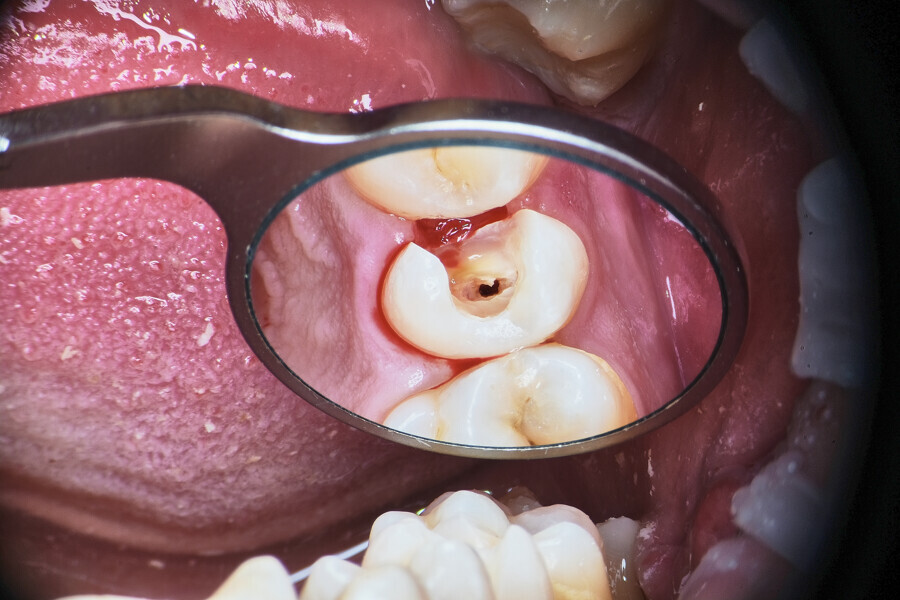

Case 3

A deep split in the canal is always challenging, especially in situations where there is compromised access or limited space. The patient came to Dr Witkowski’s dental office for a routine procedure of caries removal and restoration (Fig. 14). An initial radiograph was performed (Fig. 15). Initial removal of caries was performed, and a gingivectomy was also done owing to a deep carious lesion in the subgingival area mesially (Fig. 16). After isolation, restoration of the mesial wall was performed according to the standard protocol. After this, the access cavity was reshaped with ultrasonic tips (Fig. 17).

Instrumentation was then performed with the R25 RECIPROC blue up to the level of the split, and the split was prepared with the 12.5/0.04 R-PILOT (VDW; Fig. 18). The final irrigation protocol was performed with copious amount of fluids (sodium hypochlorite and citric acid with a final rinse of distilled water; Fig. 19). Obturation was performed with the piston technique, and the restoration was done with composite material (Fig. 20). The patient was referred to the prosthodontist for final restoration. On the final CBCT scan, it was clearly visible that the piston technique had helped to obturate the deep split in the apical area (Fig. 21).